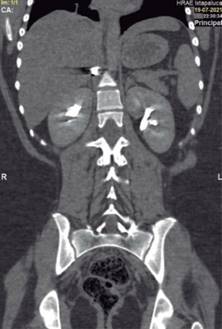

En la exploración física, sus signos vitales fueron los siguientes: frecuencia cardiaca: 74 latidos/minuto; tensión arterial: 98/67 mmHg; frecuencia respiratoria: 19/minuto, temperatura de 36 oC y saturación de oxígeno: 98%. En tórax presentaba un orificio de entrada de PAF en el cuadrante superior externo de la mama derecha (Figura 1), los campos pulmonares estaban bien ventilados. El abdomen era plano, con peristalsis, blando y sin dolor a la palpación. La biometría hemática reportó lo siguiente: hemoglobina: 12.8 g/dl, hematocrito 36.4% y leucocitos: 6,400/ml. La radiografía de tórax descartó neumotórax (Figura 2). Una TC de tórax y abdomen mostró un cuerpo extraño metálico alojado en la línea parasagital derecha a nivel de la doceava vértebra torácica (Figura 3), sin lesión pulmonar ni diafragmática (Figuras 4 y 5); en abdomen se observó un trayecto por PAF con lesión hepática grado IV de 12 cm por 2.3 cm en los segmentos IV, VII y VIII de Couinaud (Figura 5), líquido libre escaso, sin lesión de ningún otro órgano (Figuras 3, 5 y 6). Veinticuatro horas después se le realizó una TC de control, evidenciando la lesión hepática sin colección subcapsular ni extravasación activa a la aplicación del medio de contraste, sin aumento del líquido libre. Ante la correlación de estos hallazgos con la estabilidad clínica, se egresó a la paciente al cuarto día de su ingreso. Sin complicaciones un mes después de su alta.

Figura 5: Lesión hepática por proyectil de arma de fuego que penetra en el segmento VII y VIII y atraviesa el segmento IV de Couinaud, sin lesión diafragmática ni costal.